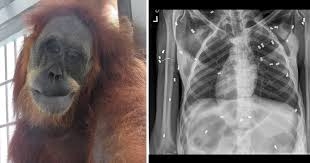

Orangutan recovers after shot with 74 airgun pellets

An orangutan is slowly recovering after being shot with 74 airgun pellets in Indonesian, an official said yesterday. The 30-year-old female was found severely wounded in Aceh province last Sunday after officials received a tipoff from villagers.

She was found in critical condition with her one-month baby under a jackfruit tree on a plantation owned by a villager. “The orangutans came to a villager’s plantation and they were considered as threats by the owner who then attempted to expel the animals,” said Sapto Aji Prabowo, chief of Aceh Conservation Agency. Officials immediately rescued the animals but the baby died from malnutrition. Almost a week later, officials say the ape, who’s been given the name Hope, is slowly recovering. “Hope is getting better, she’s starting to... eat,” Sapto Aji Prabowo said.